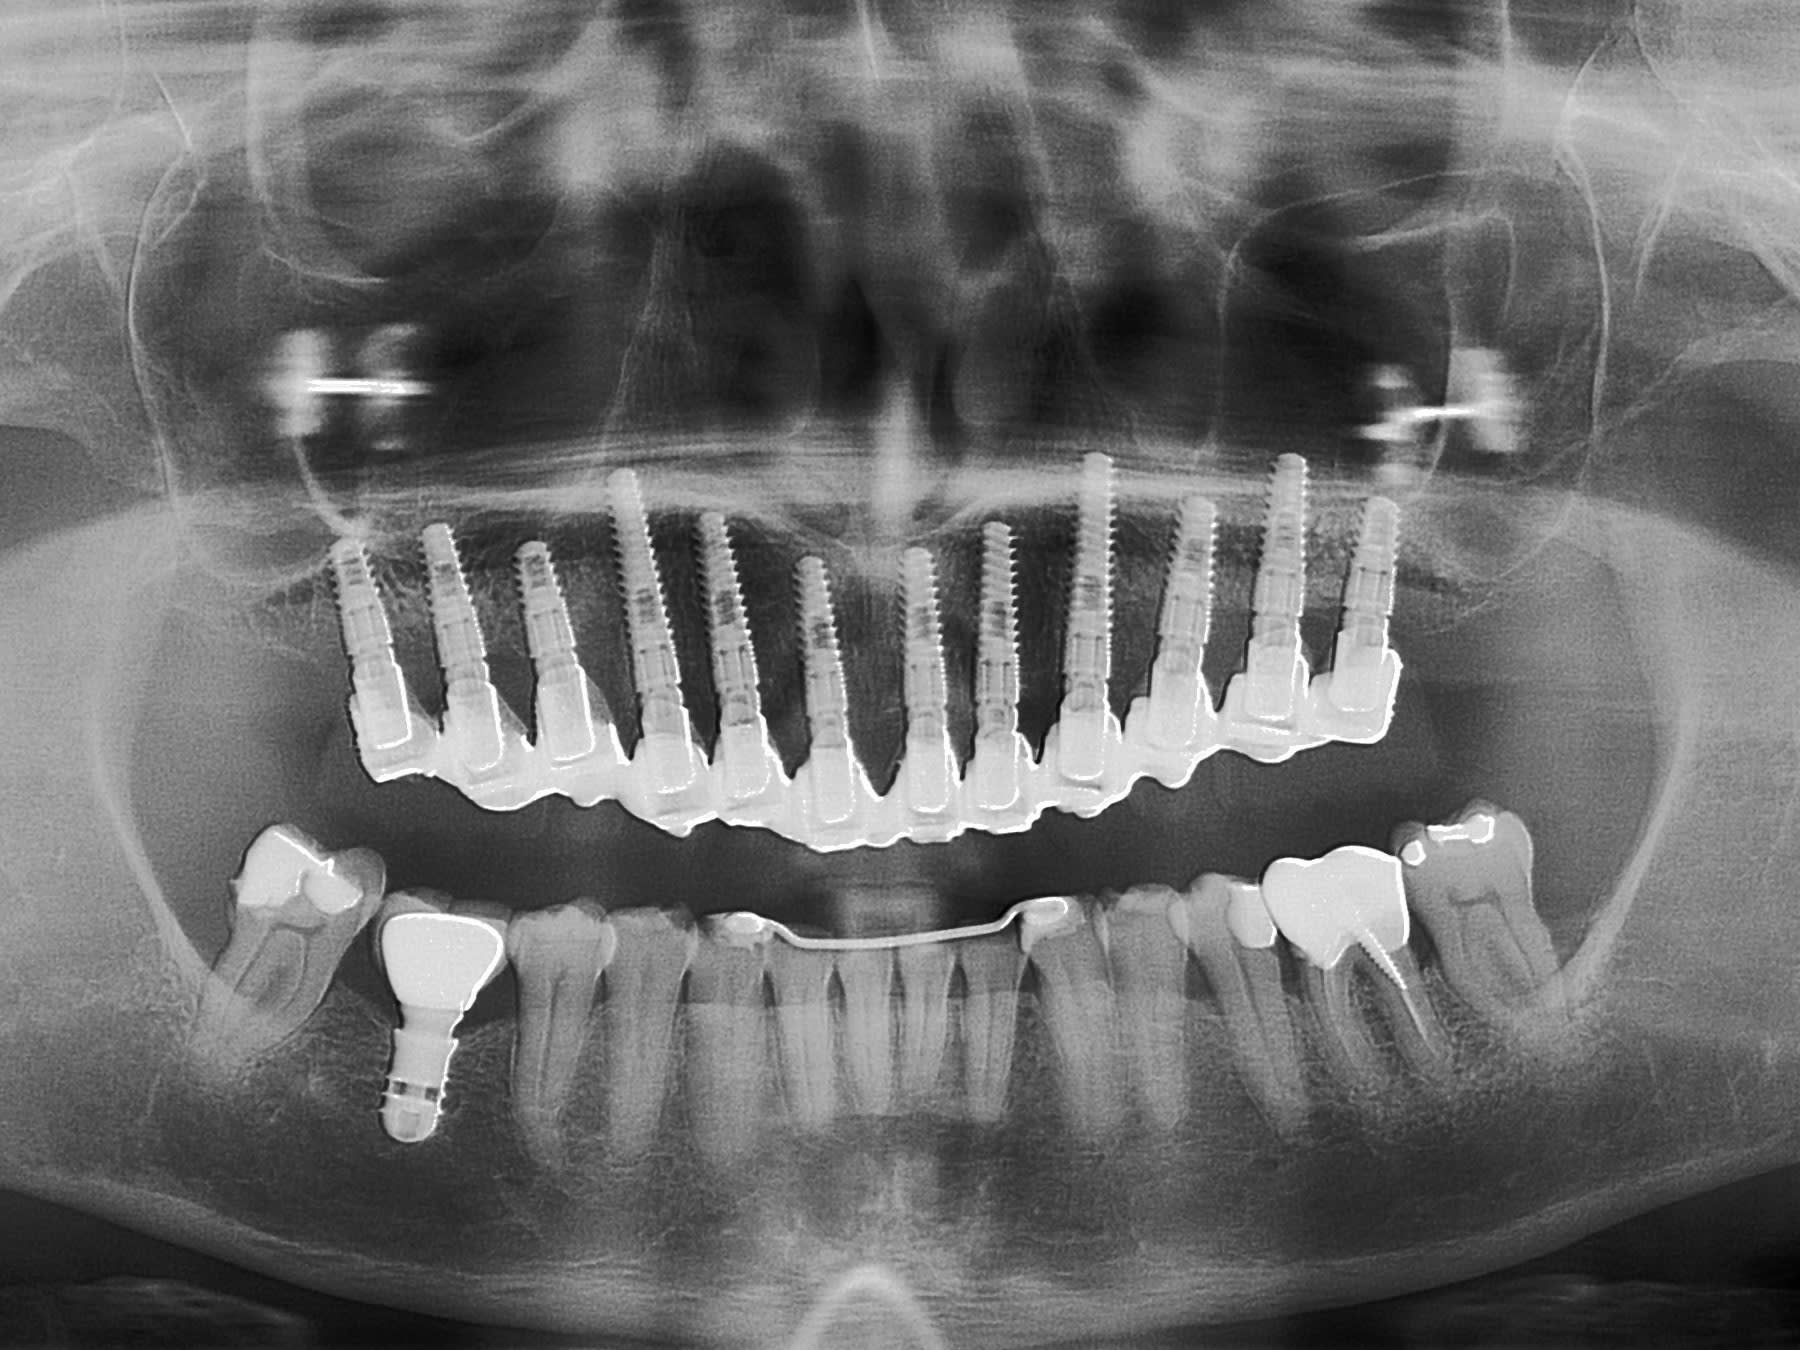

voici un bridge télescope fait en immédiat comme d'ab

réalisation pluton

Copie de pano3mois udu87e - Eugenol